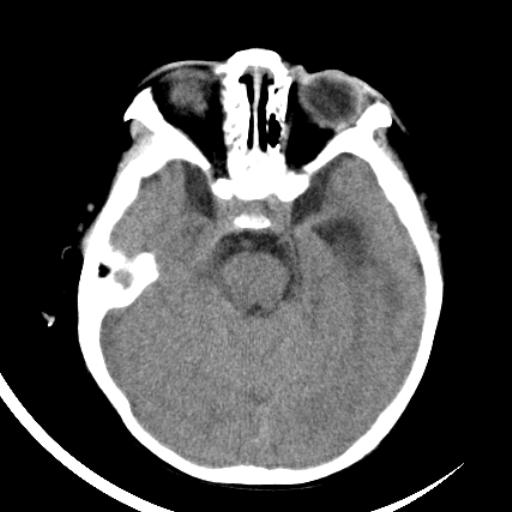

双侧脑室前后角周围白质片状低密度影,双侧侧脑室旁、双顶叶皮层及皮层下多个小原点状钙化灶,不除外torch感染。右顶叶脑回似乎较对侧大,建议mri检查以除外脑发育异常。

考虑:1、巨脑回畸形(皮质明显增厚+脑回明显增宽+白质减少)。

2、torch综合征(室管膜下钙化+白质内及皮髓质交界处多发钙化)。